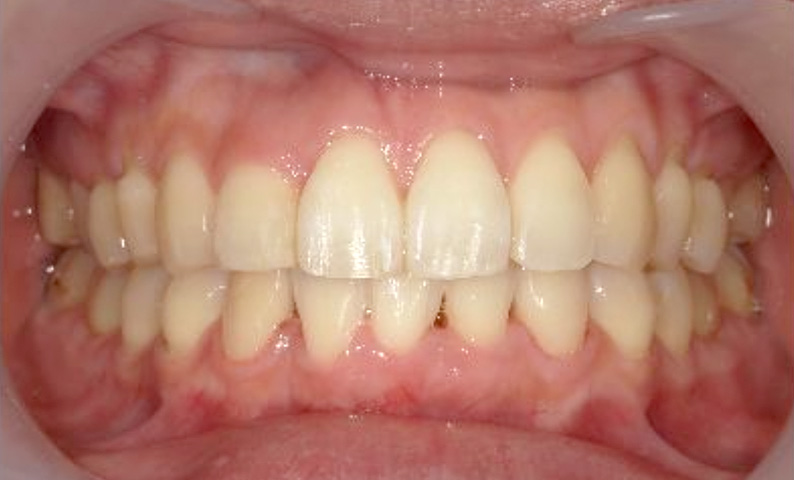

症例_002 上顎だけの部分矯正

治療期間:7ヶ月金額:30万円+税女性前歯のガタガタ上の前歯だけ

| Before | After |

|---|---|

|